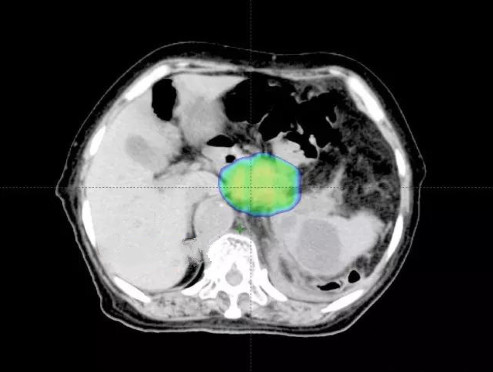

通过质子治疗病友获得质子治疗信息,为进一步诊治,来我院就诊,经全院多学科专家会诊,可行质子治疗。 质子治疗前检查图像:食道术后,腹膜后巨大肿块,累及腹腔干及分支;肿瘤大小约8.19×5.78cm,肿瘤体积为385.05cm3 ;

质子治疗剂量分布:剂量分布均匀,对周围肝脏、腹主动脉、脾脏小肠等重要组织器官起到很好的保护作用; 质子治疗三周后检查图像:肿瘤大小约6.69×5.54cm,肿瘤体积为258.2cm3,较质子治疗前体积缩小近1/3;治疗效果显著。未见明显治疗反应,病人疼痛症 状完全消失;

质子治疗前与治疗三周后图像对比: